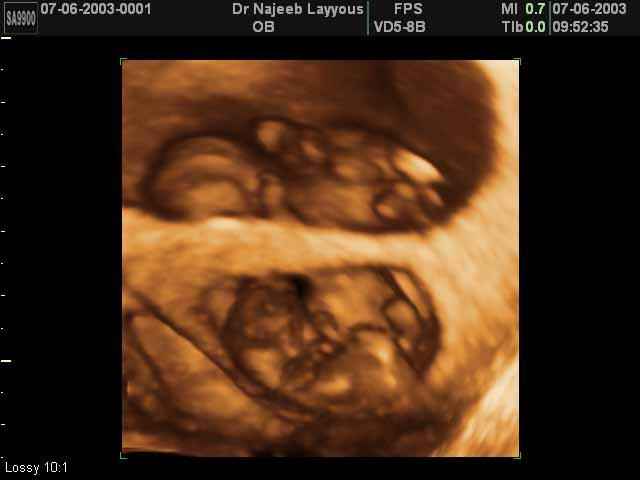

- لقطات فيديو للجنين بجهاز الموجات فوق صوتية رباعي الأبعاد

- صور لتوائم

صور لتوائم بجهاز الالتراساوند ثلاثي الأبعاد | الدكتور نجيب ليوس